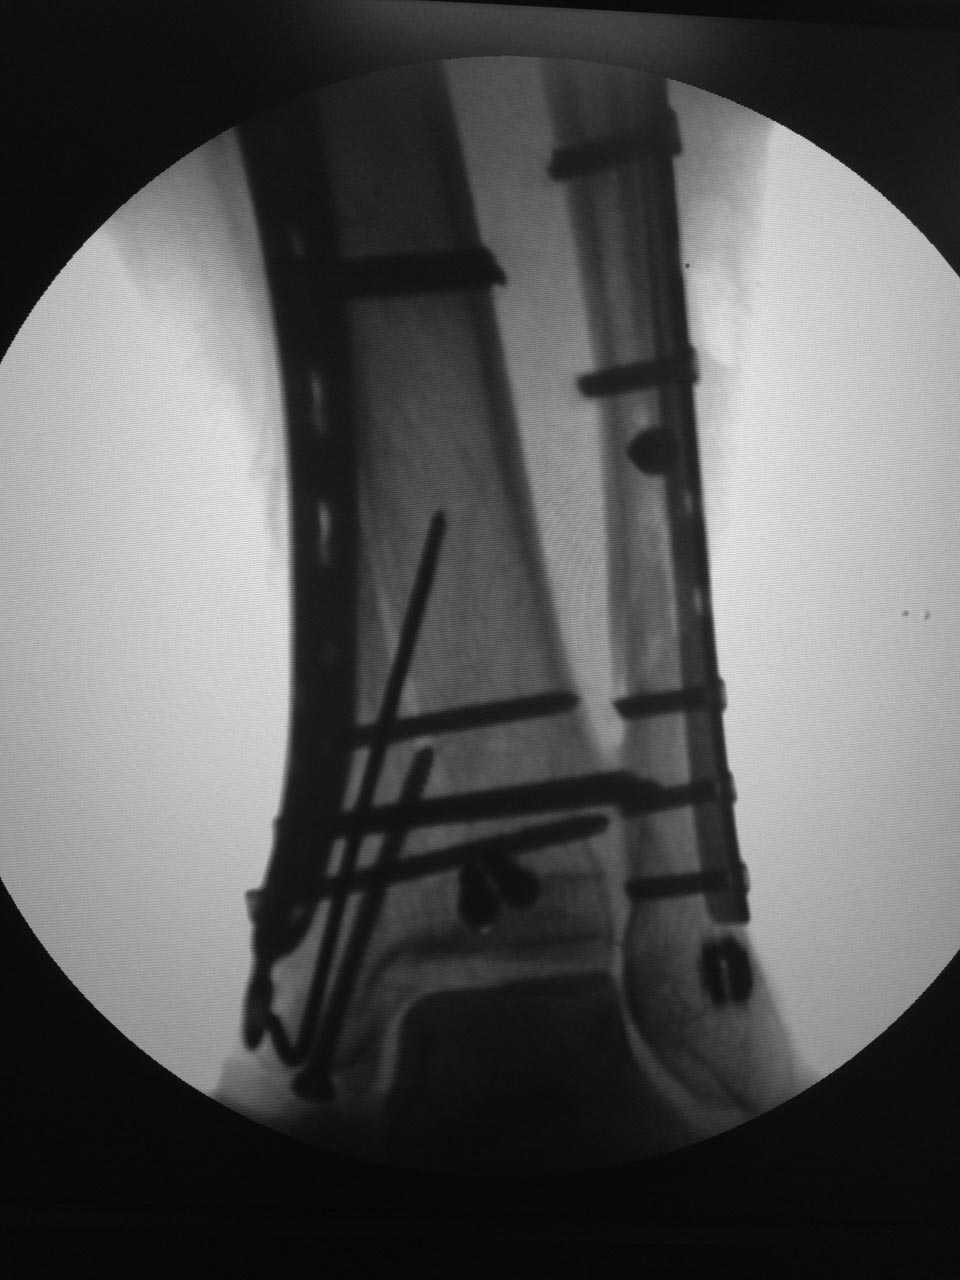

Дмитрий 19 Декабрь 2015, 00:55

Результат.

Отправитель: Дмитрий 19 Декабрь 2015, 07:53

Считаю результат удовлетворительным, начали все-таки с м/берцовой, после её фиксации задний край встал. Вторым доступом был задне-медиальный здесь обнаружился не связанный с диафизом и значительный по величине метаэпифизарный передне- медиальный отломок, его временно фиксировал спицами, затем провёл фиксацию внутренней лодыжки к этому фрагменту также спице, задний край фиксировали винтами, далее медиальная пластина, м/инвазивно(насколько возможно), затем винт во внутреннюю лодыжку. После этого проверил синдесмоз, он оказался состоятелен. На счёт что это за перелом: если бы не один передне-медиальный фрагмент, который по-суть захватывает 40-50% суставной поверхности, то без сомнений это 4 4, а так все-таки 4 3, но синтез м/берцовой считаю в этом случае был необходимым и первоочерёдным ). P.S: спасибо всем за советы, очень помогло в планировании.

Это правильно, что с малоберцовой начали и фиксировали её. Задний край, медиальный отдел. Проверка стабильности-Все ок. Правда, медиальная лодыжка кажется недорепонировпнной.

Дмитрий, по снимку не понятно, какие винты какую функцию выполняют. Есть ли винты стягивающие? Если есть, то какие?

Отправитель: Дмитрий 19 Декабрь 2015, 20:32

По суставной отрепонирована была ad ocullus, на снимках может так смотреться в следствие оскольчатого характера, стягивающий винт в пластине 4,5 мм один. Не рискнул ставить стягивающие в "ложку" побоялся "раздавить".

Дмитрий 21 Декабрь 2015, 17:14

Результат операции.

Отправитель: Alexey Semenistyy 22 Декабрь 2015, 00:33

Выглядит вполне себе не плохо. Хотя, кое-что можно было бы сделать по-другому

Отправитель: Alexey Semenistyy 23 Декабрь 2015, 01:39

Дмитрий, моя тактика была ты точно такой же.

1) Даже если бы било чем м с кем, я бы не стал делать окончательный остеосинтез в день поступления. Перелом сложный (44С с претензией быть 43В), больная тучная, значит энергия травмы приличная, несмотря на непрямой ротационный главным образом механизм, и мягкие ткани могут быть скомпроментированы. В первые часы это оценить трудно, можно только предположить. Аккуратная, не грубая закрытая репозиция и наружный фиксатор в положении приблизительной репозиции - это то, что я сделал при поступлении, примерно так же как и вы и это сделали.

2) Я бы все делал в таком же порядке: малоберцовую и задний край, затем медиальный раскол, в последнюю очередь медиальную лодыжку. Оценка стабильности синдесмоза.

КТ, безусловно, показана, но только после репозиции и в аппарате

Иначе я бы поступил с направлением некоторых винтов, с их функцией (см вложение):

1)Винты, фиксирующие задний край, должны быть стягивающими, приходить перпендикулярно плоскости перелома.

2)Нужен хотя бы один стягивающий винт вне или через опорную пластину для вертикального метаэпифизарного раскола параллельно суставной поверхности (в прямой проекции) и достаточно близко к ней.

3) Винт через внутреннюю лодыжку также должен быть стягивающим. Направление и длину его я бы выбрал такое, чтобы он заканчивался не в зоне вертикального разлома, не в зоне перехода метафиза в диафиз, где в центре кости уже мало губчатого вещества, а более дистльно и вертикально , где "губка" более плотная. Возможно, стягивание петлей по Веберу здесь более предпочтительно.. Ну и с открытой репозицией медиальной лодыжки постарался бы...

3) В качестве опорной пластины для медиального раскола взял бы 1/3-трубки, ну в крайнем случае максимум 3,5 метафизарную LCP. "Ложка" тут избыточна, а вот стягивающего винта не хватает.

Отправитель: Paul 24 Декабрь 2015, 08:09

На ренгенограмме в сагитальной проекции контуры кортикальной пластинки внутренней лодыжки не совпадают - в месте перелома, а на сагитальной проекции, кажется, смещение внутренней лодыжки кпереди....

Re: Травма голеностопного сустава 44С3 помогите определиться с оперативной тактикой

сергей 28 Декабрь 2015, 19:52

Интересно бы сделать снимки обоих голеностопов на одной кассете и посмотреть синдесмоз на здоровой конечности. Какое-то ощущение, что имеется небольшой подвывих...